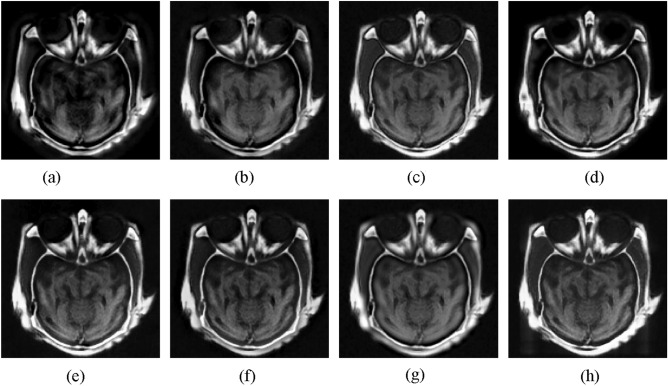

The first experiment is to fuse CT and MRI images. Figure 3 presents the fusion images obtained by different methods. As shown in Fig. 3, the CNN-NSCT method leads to some loss of local details. The NSST method yields low contrast fusion result. The NSST-ST method fails to well fuse the information of source CT image. The fusion result obtained by SR method appears distortion phenomenon. The MST-SR method suffers from the detail loss of source MRI image. The GFF method decreases the brightness of source MRI image. Although the DSWT-RBFN method retains well the information of original images, the boundaries in the fused image are blurry. In comparison, the proposed method can retain the detail information of original images. In addition, the boundaries in the fused result are visible clearly.

Figure 3.

Fusion results of different methods for CT and MRI images. (a) CNN-NSCT. (b) NSST. (c) NSST-ST. (d) SR. (e) MST-SR. (f) GFF. (g) DSWT-RBFN. (h) Our method.

To illustrate objectively the fusion quality of resulting images achieved by different approaches, Table 1 shows the average objective metrics on 11 pairs of CT and MRI images. It can be seen from Table 1 that the proposed approach yields the highest objective indexes in terms of SD, EN, QMI, and QPC, which further proves that the proposed method can effectively achieve the CT and MRI image fusion over other methods. For the computational time, it is show that the running time of the proposed method is acceptable among all studied techniques. Moreover, compared to the CNN-NSCT, the proposed method performs faster.